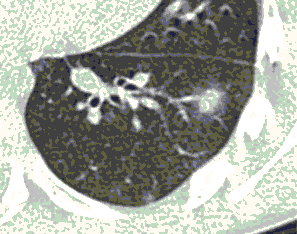

КТ имеет высокую чувствительность в выявлении изменений в легких, характерных для COVID-19. Применение КТ целесообразно для первичной оценки состояния ОГК у пациентов с тяжелыми прогрессирующими формами заболевания, а также для дифференциальной диагностики выявленных изменений и оценки динамики процесса. КТ позволяет выявить характерные изменения в легких у пациентов с COVID-19 еще до появления положительных лабораторных тестов на инфекцию с помощью МАНК. В то же время, КТ выявляет изменения легких у значительного числа пациентов с бессимптомной и легкой формами заболевания, которым не требуется госпитализация. Результаты КТ в этих случаях не влияют на тактику лечения и прогноз заболевания при наличии лабораторного подтверждения COVID-19. Поэтому массовое применение КТ для скрининга асимптомных и легких форм болезни не рекомендуется. При первичном обращении пациента с подозрением на COVID-19 рекомендуется назначать КТ только при наличии клинических и инструментальных признаков дыхательной недостаточности (SpO2 < 95%, ЧДД > 22).

4. Все выявляемые при лучевых исследованиях признаки, включая КТ-симптомы, не являются специфичными для какого-либо вида инфекции и не позволяют установить этиологический диагноз. Вне клинической (эпидемической) ситуации они не позволяют отнести выявленные изменения к пневмонии COVID-19 и дифференцировать их с другими пневмониями и невоспалительными заболеваниями. Данные лучевого исследования не заменяют результаты обследования на РНК SARS-CoV-2. Отсутствие изменений при КТ не исключает наличие COVID-19 и возможность развития пневмонии после проведения исследования.